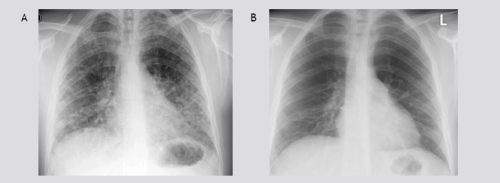

A 22-years old male presented with dyspnea, non-productive cough, myalgia and fever. These symptoms started 4 days prior to admission. His medical history was unremarkable. He smoked tobacco for a few years. Finally, he admitted alcohol abuse, heavy marijuana and cocaine smoking in the last months. Physical examination revealed some crackles at auscultation, he was a little tachypnoeic (20 breaths•min–1) and his body temperature was 36.8°C. He had a moderate hypoxemia (pO2 8.7kPa, breathing room air), high serum C-reactive protein (254 mg/l), a white blood cell count of 16.3 109•L–1 and a normal number of eosinophils. Figure 1 shows his chest roentgenogram demonstrating diffuse infiltrates at presentation. Figure 2 shows his high resolution CT (HRCT) scan with a diffuse reticulonodular pattern ad admission. Spirometry two days after admission showed normal dynamic lung volumes with slightly decreased diffusing capacity (81% of predicted).

Figure 1 A) Chest radiograph at admission shows parenchymal lung opacities; B) Two weeks after admission, normalized.

The patient was initially treated with a broad-spectrum antibiotic, moxifloxacine intravenously, aiming to cover the majority of common and atypical microbes. Because of high suspicion of a ‘drug’-induced interstitial lung disease (DI-ILD) and the absence of features of any infectious cause, corticosteroids were started (40mg daily, i.v.) and continued for two weeks. Thereafter, the corticosteroids were tapered gradually. His clinical condition improved within 2 weeks. Dyspnea and cough disappeared, follow-up chest radiograph abnormalities cleared (figure 1B) and the PaO2 became within normal limits (11.9 kPa; on room air at rest).